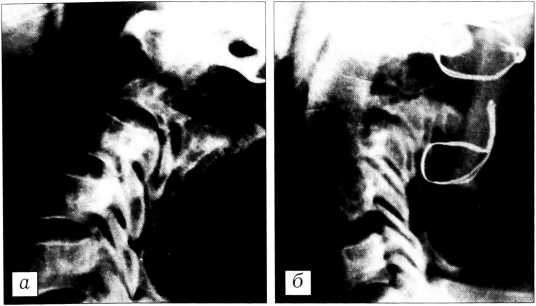

Костно-хрящевые экзостозы (солитарные или множественные) составляют 18,5%. Встречаются у лиц молодого возраста. Экзостоз исходит из элементов дуги. Клинически проявляется безболезненной припухлостью, спаянной с костью, может вызывать радикулярные боли и с течением времени быстро расти. В отличие от костно-хрящевого экзостоза длинных костей, у экзостоза позвоночника ножка более плотная, чем остальная часть. Иногда новообразование достигает больших размеров и имеет вид «цветной капусты» (рис. 1).

Рис. 1. Больная Б. 11 лет. Новообразование, исходящее из дуги L4 (а), распространяется от подвздошной кости до XI ребра (б), имеет вид «цветной капусты» (в). Новообразование удалено с частью дуги L4. Гистологическое исследование: костно-хрящевой экзостоз.

Гистологически состоит из губчатой кости, покрытой слоем гиалинового хряща. При быстром росте выражены признаки атипизма и полиморфизма клеток гиалинового хряща у основания экзостоза. Поэтому резекция должна производиться не у основания, а вместе с дугой или отростком. Нередки случаи малигнизации при агрессивном росте.